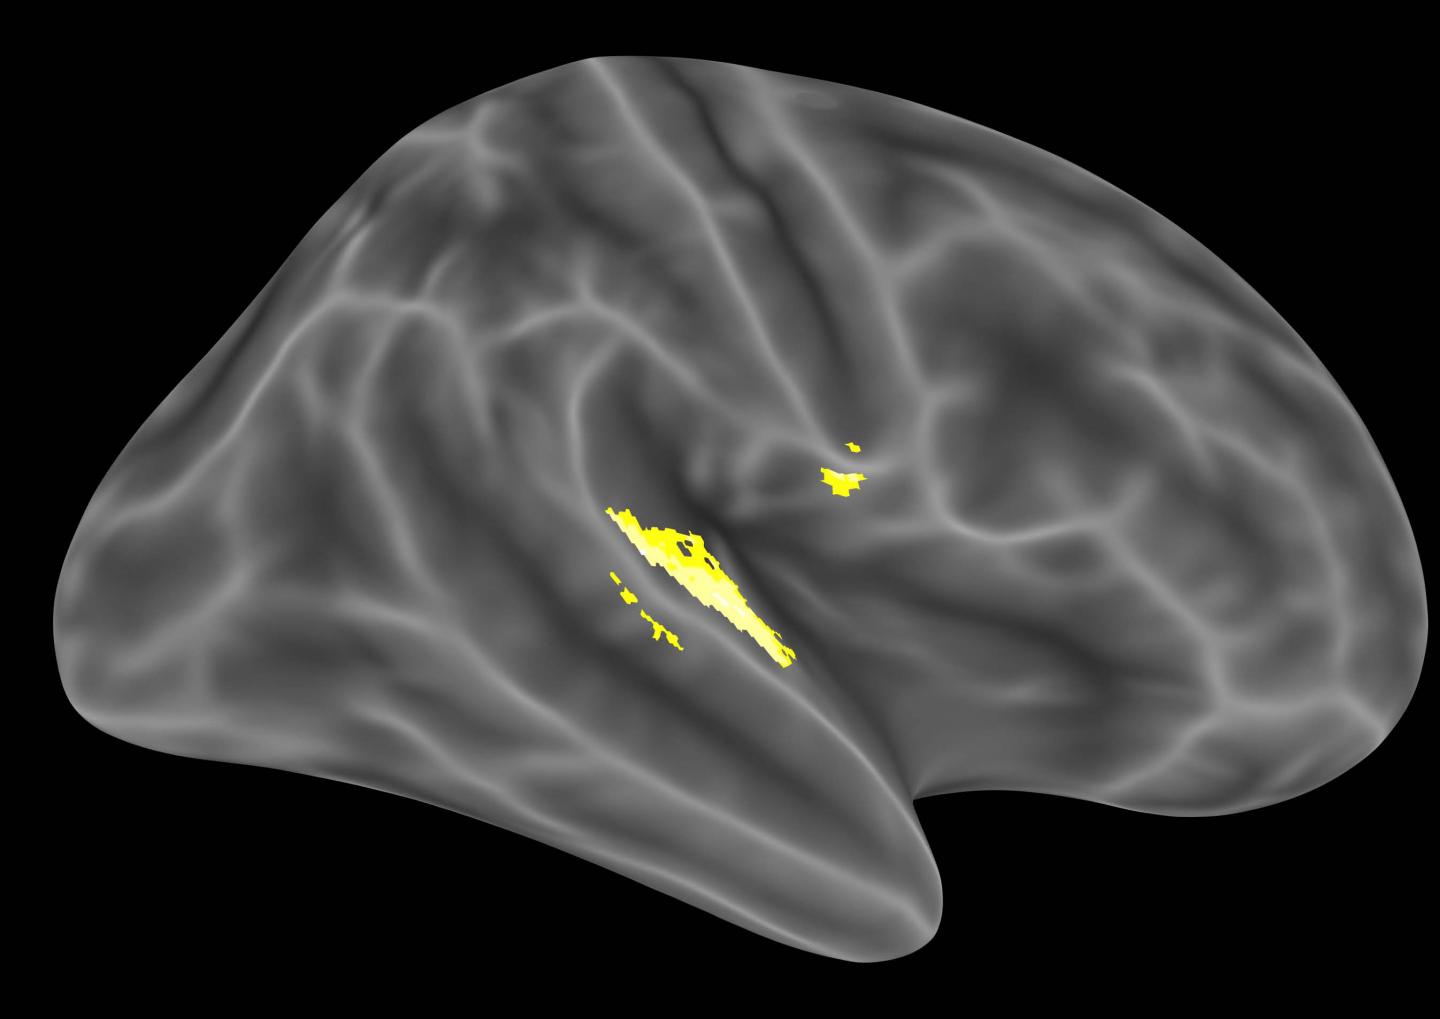

image: A lateral view of brain regions that are sensitive to tones of fluctuating intensity. This material relates to a paper that appeared in the 11 August 2017, issue of <i>Science</i>, published by AAAS. The paper, by A.R. Powers at Yale University School of Medicine in New Haven, CT, and colleagues was titled, "Pavlovian conditioning-induced hallucinations result from overweighting of perceptual priors." view more

Credit: Albert Powers, Chris Mathys & Phil Corlett